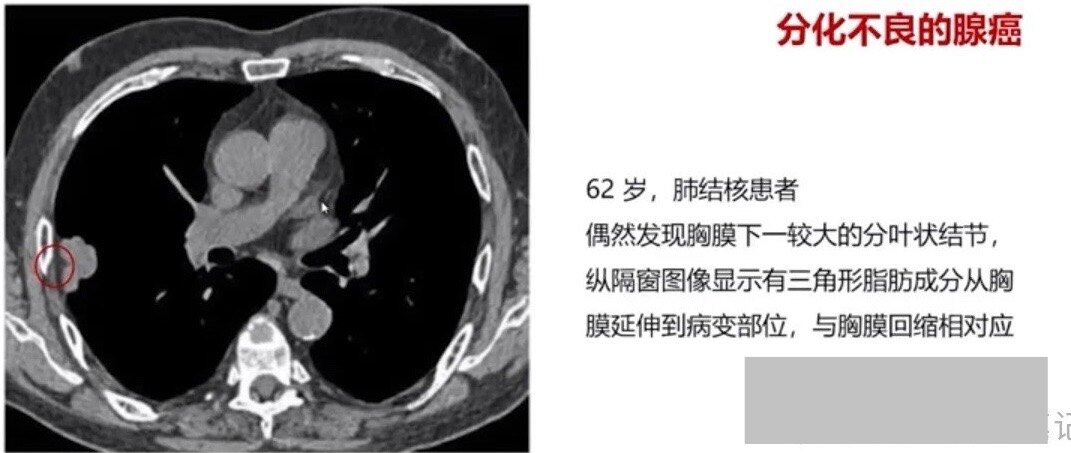

有结节是肺癌吗_有结节是肺癌吗